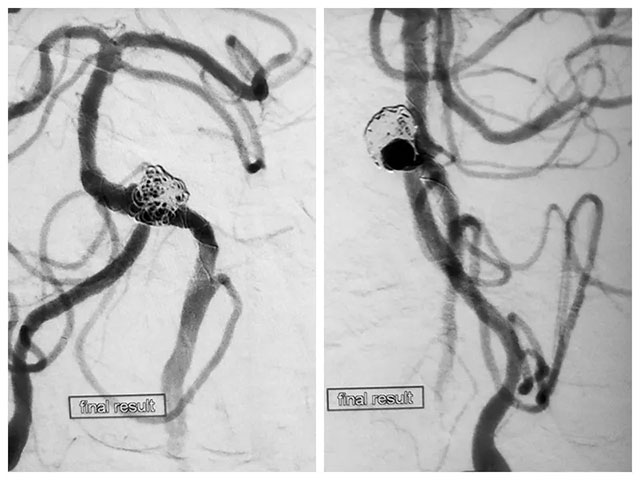

先向瘤体内稀疏填入一枚弹簧圈,随后释放支架至覆盖瘤颈,随后通过支架网孔继续向瘤腔内填入数枚弹簧圈,再次造影见大部分瘤体不显影。但子瘤内仍可见少量血流,通过支架导管再次释放一枚支架覆盖瘤颈,再次造影后见动脉瘤无显影,撤出系统后行血管造影,未见血栓形成,CT检查无出血。

DSA造影手术、左侧椎动脉闭塞开通手术、支架辅助弹簧圈栓塞手术处理夹层动脉瘤和子瘤,这位病患先后进行了四次手术,历时近12小时,最终完成血管内重建性治疗。

▲ 术后造影